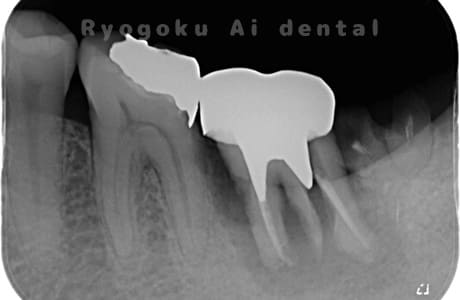

Case07

-

- 原因

- 右下6番歯根破折

- 治療内容

- インプラント治療

- 治療費用

- 約600,000円

右下の腫れが治らないとの事でご来院された患者様です。歯が割れていたため、抜歯を行い、骨に代わるお薬を入れ、インプラントを埋入致しました。経過良好で大変満足していただけました。

<リスク・副作用>

治療後、痛みや違和感、出血、腫れなどが出る事があります。喫煙者、糖尿病などの方の場合、歯が生着しない場合があります。